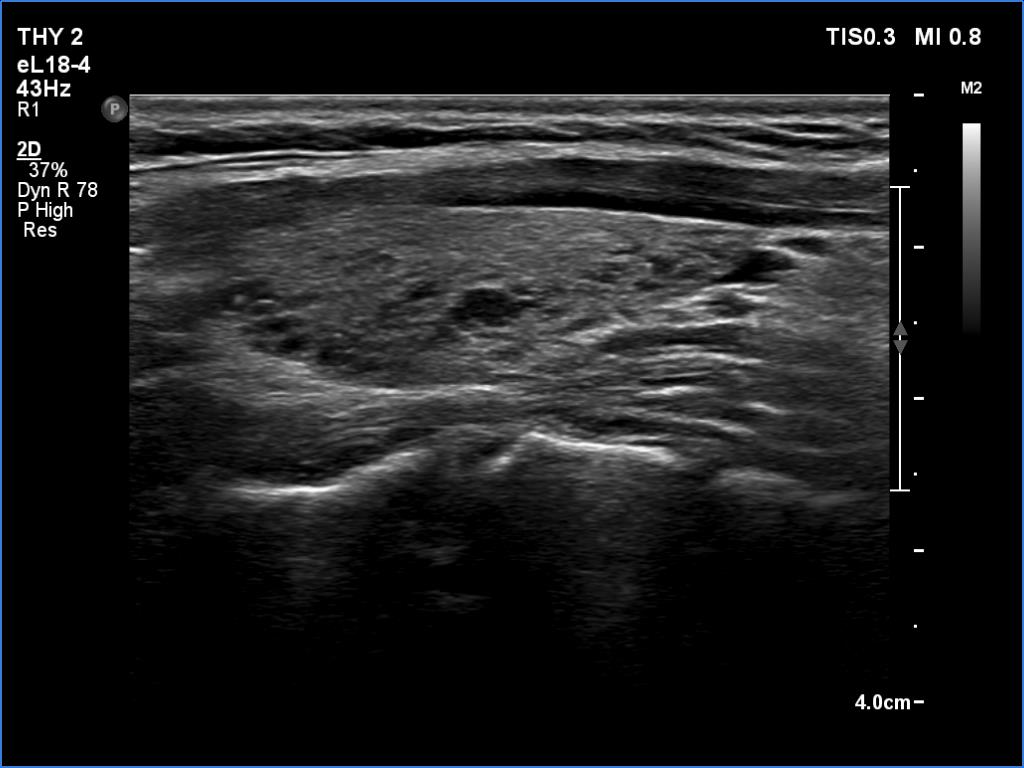

Right lobe, longitudinal scan

Left lobe, longitudinal scan. This pattern is pathognomonic, the patient has autoimmune thyroiditis.